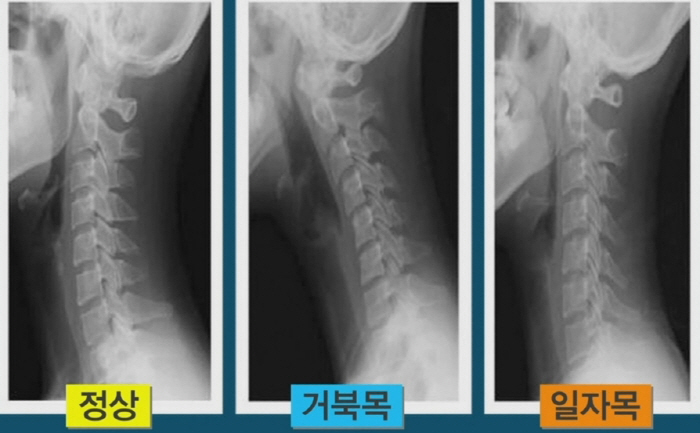

생활 습관 또한 목디스크 관리에 큰 영향을 미칩니다. 바른 자세를 유지하는 것이 중요하며, 잘못된 습관이 축적되면 목디스크의 원인이 될 수 있습니다. 평소 앉을 때는 등과 목을 곧게 펴고, 모니터의 위치를 눈 높이에 맞추는 것이 좋습니다.

또한, 컴퓨터 사용 중에는 주기적으로 스트레칭을 하는 것이 좋습니다. 30분마다 잠시 일어나서 몸을 움직이면 근육의 긴장을 줄이는 데 효과적입니다. 이런 작은 습관들이 목디스크 예방에 큰 도움이 될 수 있습니다.